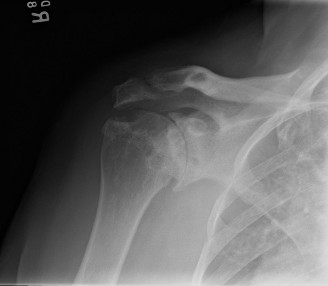

A 19-year-old, collegiate offensive lineman presents to your clinic with vague shoulder pain that has been on…